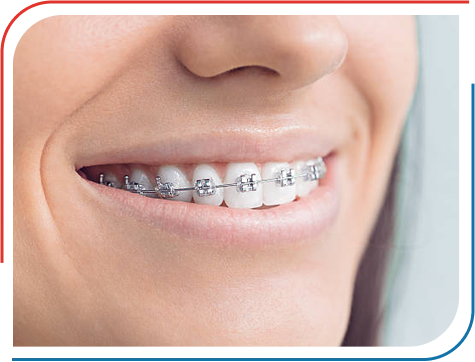

Root Canal Treatment

Root canal treatment, often referred to as endodontic therapy, is a dental procedure used to treat and save a tooth that has become infected or severely damaged due to decay or injury.